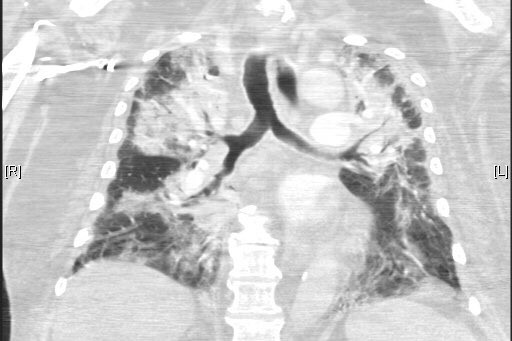

RT @Doc_B_LE

ist auch auf unserer Intensivstation angekommen.

Schwerst hypoxämischer Patient (71). Lactat normal, pH 7,1 bei BE -13.

CoronaPCR hoch positiv (ct 16).

Wir sehen wieder eine Zunahme schwerer -Pneumonien. Die aktuellen Lockerungen sind eine sehr dumme Entscheidung!